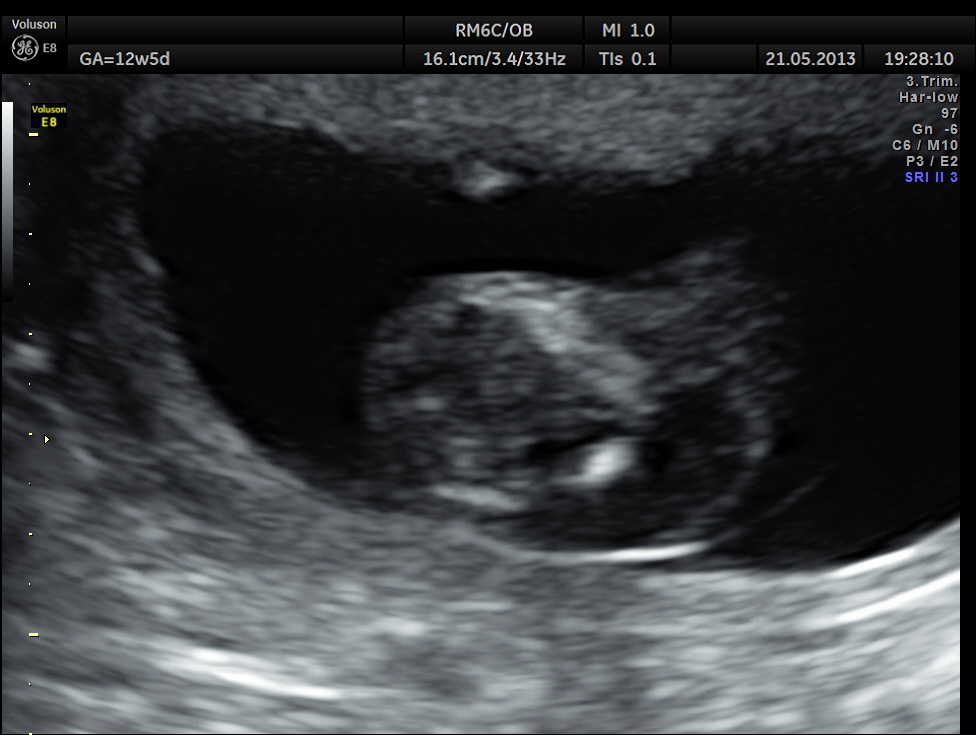

This 23 year old primi gravida, with no history of consanguinity was referred for 2nd opinion for evaluation of cystic swelling of the neck in the first trimester.

The following are the 2 d pictures.

The diagnosis offered was cystic hygroma .